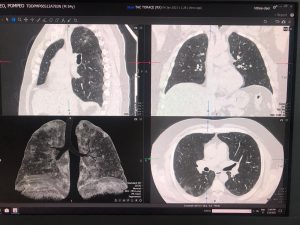

Per conoscere il quadro polmonare nel periodo successivo alla fase di polmonite virale, il Servizio di Diagnostica per Immagini del Fatebenefratelli di Benevento, diretto dal dott. Carmine Manganiello, ha applicato un protocollo di studio del torace con la TAC di ultima generazione in grado di predire l’evoluzione verso la fibrosi polmonare e prevenirne le conseguenze.

Questo percorso consente di apprezzare le alterazioni della struttura polmonare simili alla fibrosi e di confrontare il volume polmonare ben areato con il volume polmonare interessato dalle lesioni della pregressa polmonite interstiziale.

Attraverso la valutazione TAC di tipo quantitativo del torace dei pazienti guariti dalla polmonite interstiziale da COVID-19 è possibile dare indicazioni allo pneumologo e al fisiatra circa la terapia più appropriata per prevenire la fibrosi polmonare.